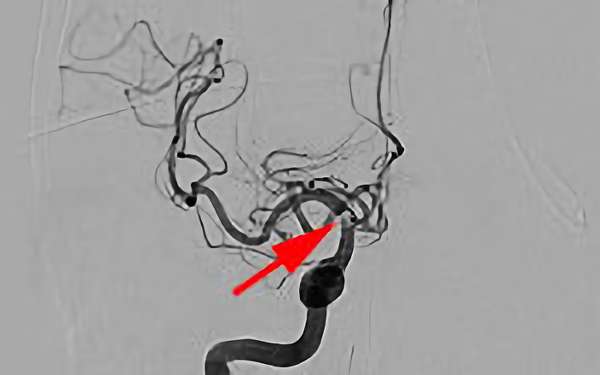

No.1630 手術前